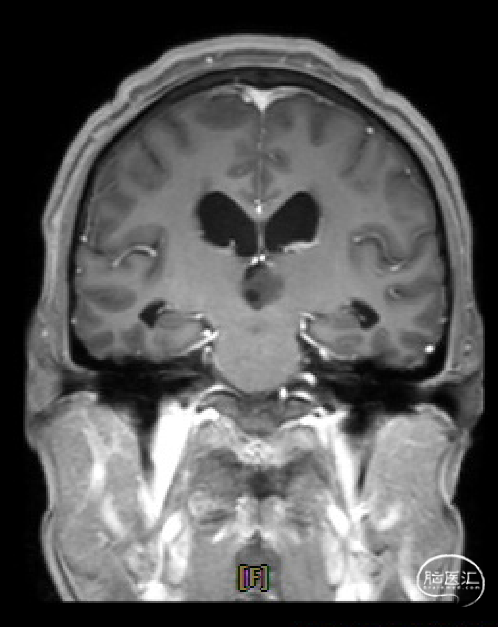

患者5年前无明显诱因出现阵发性头晕,无明显头痛、恶心呕吐等不适,开始未予重视,2022-7-19出现头晕加重,伴视力下降,遂于2022-7-24在当地医院行颅脑MRI提示:松果体区肿瘤伴梗阻性脑积水。

于该院在2022-7-27全麻下行松果体区病灶部分切除活检+神经内镜下第三脑室底造瘘术,术后由于取出肿瘤组织少,未能明确病理结果。患者术后恢复顺利,为进一步治疗就诊于我院。

枕下后正中开颅经幕下小脑上入路松果体区肿瘤切除术。

术前MRI与术后复查MRI对比